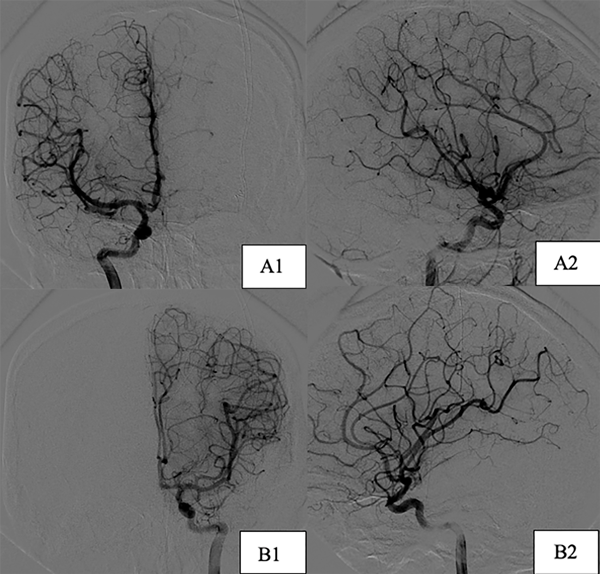

Paciente de sexo femenino, de 17 años, sin antecedentes patológicos, a quien en contexto de estudio por episodio de crisis comiciales de novo se le diagnostican dos MAVs supratentoriales, una frontal derecha de 25 x 29 mm diámetro, con aferencias silvianas, de nido compacto y drenaje hacia el seno longitudinal superior a través de gran vena cortical y otra temporal izquierda de 16 x 11 mm con aferencias silvianas, de nido compacto y drenaje hacia el seno transverso, sin evidencia de signos sugestivos de sangrado (Figura 4). Se decidió estudiar y descartar síndromes congénitos para luego programar la cirugía. Debido a que ninguna de las dos lesiones presentaba factores angiográficos de rotura y por su localización en el hemisferio no dominante se decidió abordar inicialmente la malformación frontal derecha (Figura 5) y 7 meses después se realizó la exéresis de la restante con control angiográfico postquirúrgico satisfactorio y ninguna complicación asociada (Figura 6).

Figura 6. Imágenes postoperatorias caso 2. Incidencias derechas. A1) Corte coronal. A2) Corte sagital. B) Incidencias izquierdas. B1) Corte coronal. B2) Corte sagital.

DISCUSIÓN